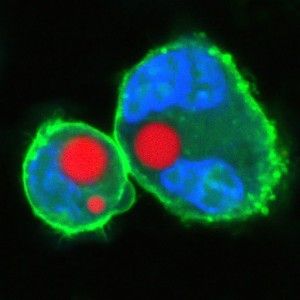

Yun's team did this in two different ways. A soft version was made by injecting a small drop of oil or natural fat lipids mingled with a fluorescent dye into a cell. A hard version used fluorescent polystyrene beads instead. In each case, the entire cell was excited by a nanosecond pulse that produced light, which then became trapped inside the sphere.

The extreme precision of that output is one thing that makes the tiny lasers so promising. The soft droplet versions shift shape ever so lightly when under stress, and that deformation makes a visible change in the laser's emission spectrum, so that even minute changes in the cell can be recorded in fine detail. Similarly the team can produce lasers of slightly different wavelengths by changing the size of the hard beads—enabling them to uniquely color code an individual cell and potentially label thousands of different cells within a single tissue, according to the research published this week in Nature Photonics.

Living cells are the ideal delivery mechanism for getting these microlasers where they can do the most good. For example, immune cells can be targeted to respond to specific problems, so they could deliver a laser to bind with a tumor or other disease location. Once in place, a finely tuned laser light could perform any number of applications.